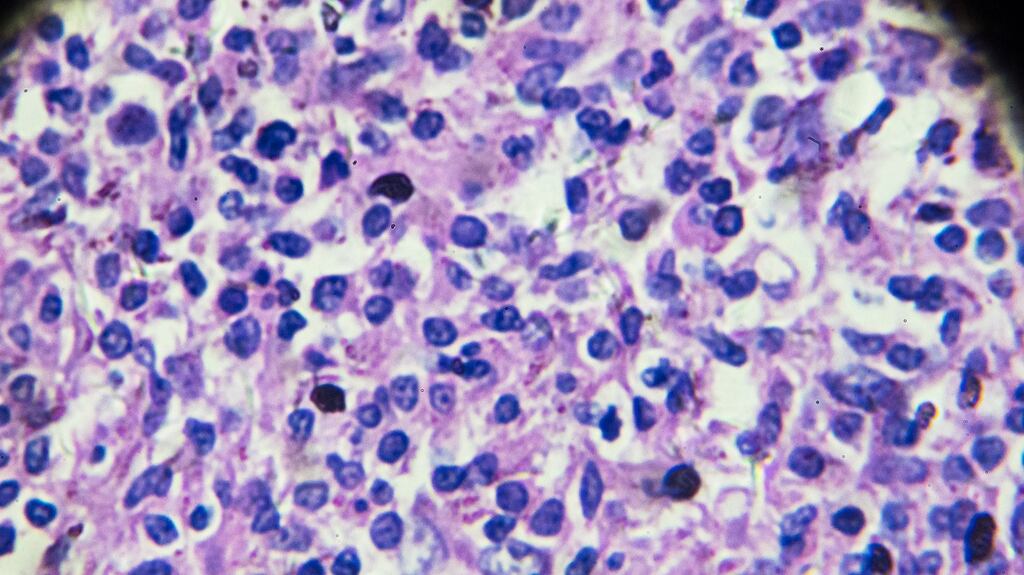

Drug-delivery business Avectas has licensed a therapy from Galway-based ONK Therapeutics that targets what are called B-cell malignancies – blood cell cancers such as non-Hodgkin's lymphoma and certain forms of leukaemia.

ONK has developed a process that genetically engineers natural killers cells – part of the body's immune system – to allow them better pursue cancer cells that have made themselves invisible to normal natural killer cells.

It has also added genetic material that makes the engineered cells more toxic for the target cancer cells, delivering a more effective therapy.